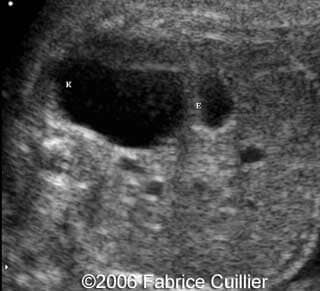

This is a 24- year-old-primigravida scanned at our unit at 21 weeks. During the first trimester, the nuchal translucency and the triple test were normal. At the end of the second trimester, the sonographer diagnosed a left polycystic kidney. The right kidney was normal with a normal corticomedular differentiation. The bladder was also normal. The patient refused additional investigations. We performed a scan at 21 weeks. The ultrasound findings were:

• an abnormal polycystic left kidney (34 X 17 mm) with an abnormal corticomedullar differentiation. This kidney was on the lumbar fossa.

Transverse view of the normal right kidney and the abnormal left kidney